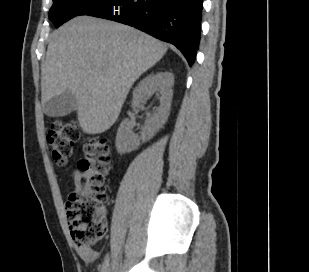

Компьютерная томография позволяет детально визуализировать структуру лимфатических узлов, выявить ее неоднородность, гиперплазию, определить деформацию контуров, появление инфильтрации окружающих тканей с образованием пакетов и конгломератов лимфоузлов.

В ходе сканирования врач оценивает структуру, размеры, плотность, контуры лимфатических узлов этих анатомических областей. Изменения этих параметров могут указывать на: